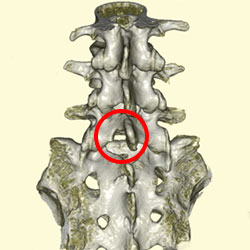

CT

CT